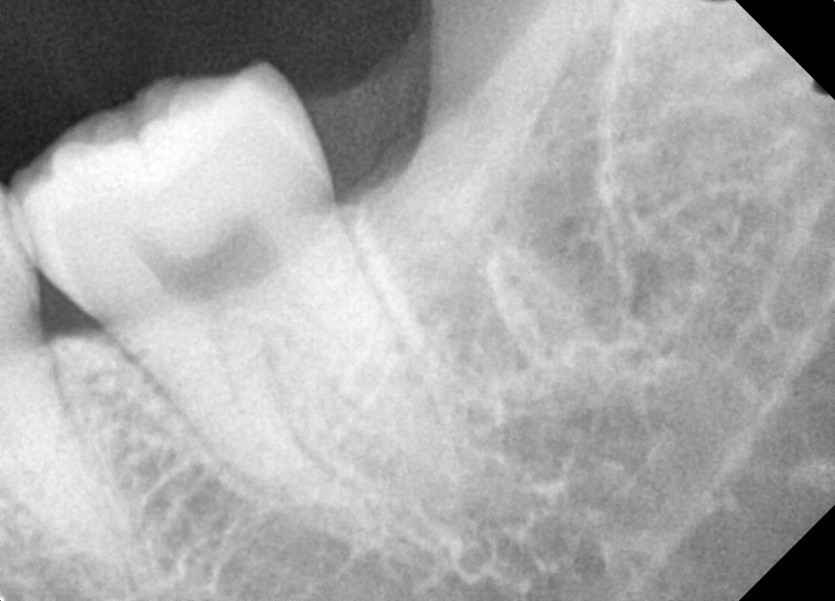

#38 사랑니 발치

구강 외과 전문의가 당일 발치했습니다.